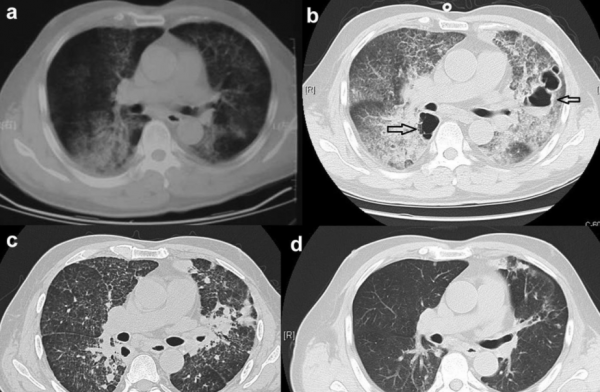

一項一項檢查做完了,血常規、二便常規即血糖血脂凝血等指標一切正常,胸部CT可見左上肺佔位,增強未見明顯強化,縱膈可見多個增大的淋巴結。肺功能一切正常,肝膽胰脾一切正常。

原來,而後續的針對性的馬爾尼菲藍狀菌檢查也驗證了陳女士就是感染了罕見的馬爾尼菲青黴菌,繼而導致嚴重的面板化膿性感染及肺部病變。